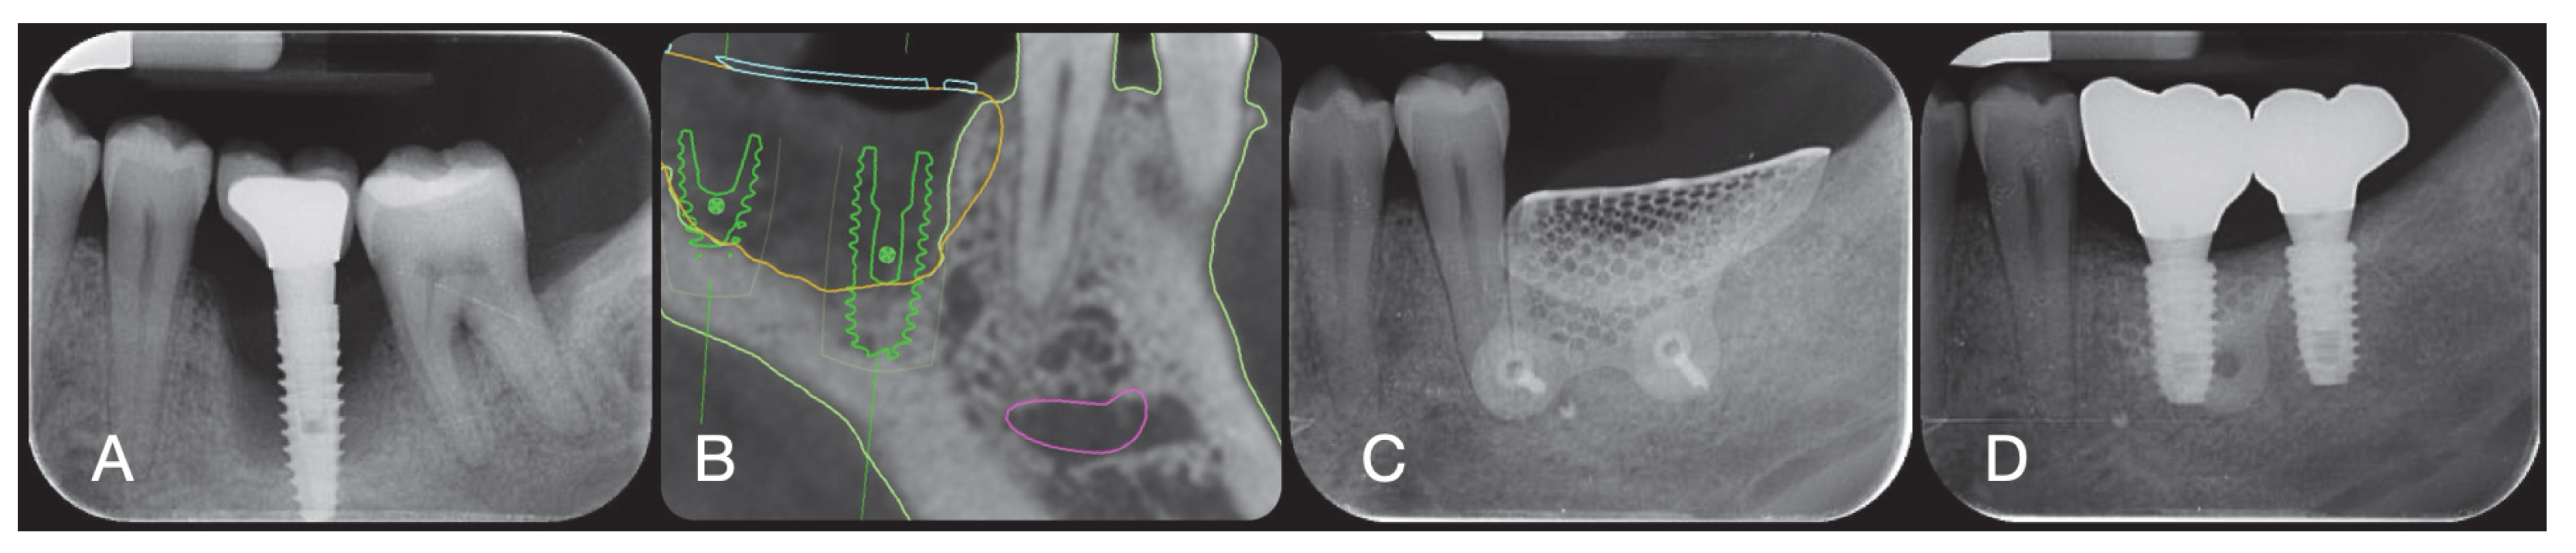

2.5. GBR Procedure

3.1. Clinical Outcomes